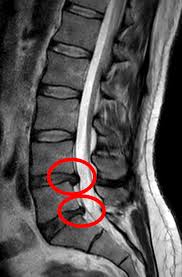

Pentru foarte mulți oameni, momentul în care primesc rezultatul unui RMN este șocant. Pe foaie scrie: „hernie de disc”. În acel moment apare inevitabil gândul: „Asta este cauza durerii mele de spate.”

Hernia de disc apare atunci când o parte din nucleu iese prin inelul fibros.

Acest lucru poate duce la:

- iritarea unei rădăcini nervoase

- inflamație locală

- modificări mecanice în jurul nervului

Și atunci poate apărea durerea.

Dar cheia este cuvântul „poate”.

Una dintre cele mai importante descoperiri din ultimele decenii este că hernia de disc apare frecvent și la oameni fără durere.

Un review sistematic publicat în American Journal of Neuroradiology a analizat mii de RMN-uri ale unor persoane fără dureri de spate.

Rezultatul a fost surprinzător:

- peste 30% dintre persoanele de 30 de ani aveau hernii sau protruzii discale

- procentul crește odată cu vârsta

- mulți dintre acești oameni nu aveau niciun simptom

Cu alte cuvinte:

o hernie pe RMN nu înseamnă automat că ea este cauza durerii.

Dar hernia este încă vizibilă pe RMN.

Acest lucru este perfect posibil.

- dar hernia de disc rămâne vizibilă pe RMN.

Imaginea de pe RMN reprezintă structura, dar durerea este rezultatul interpretării sistemului nervos.